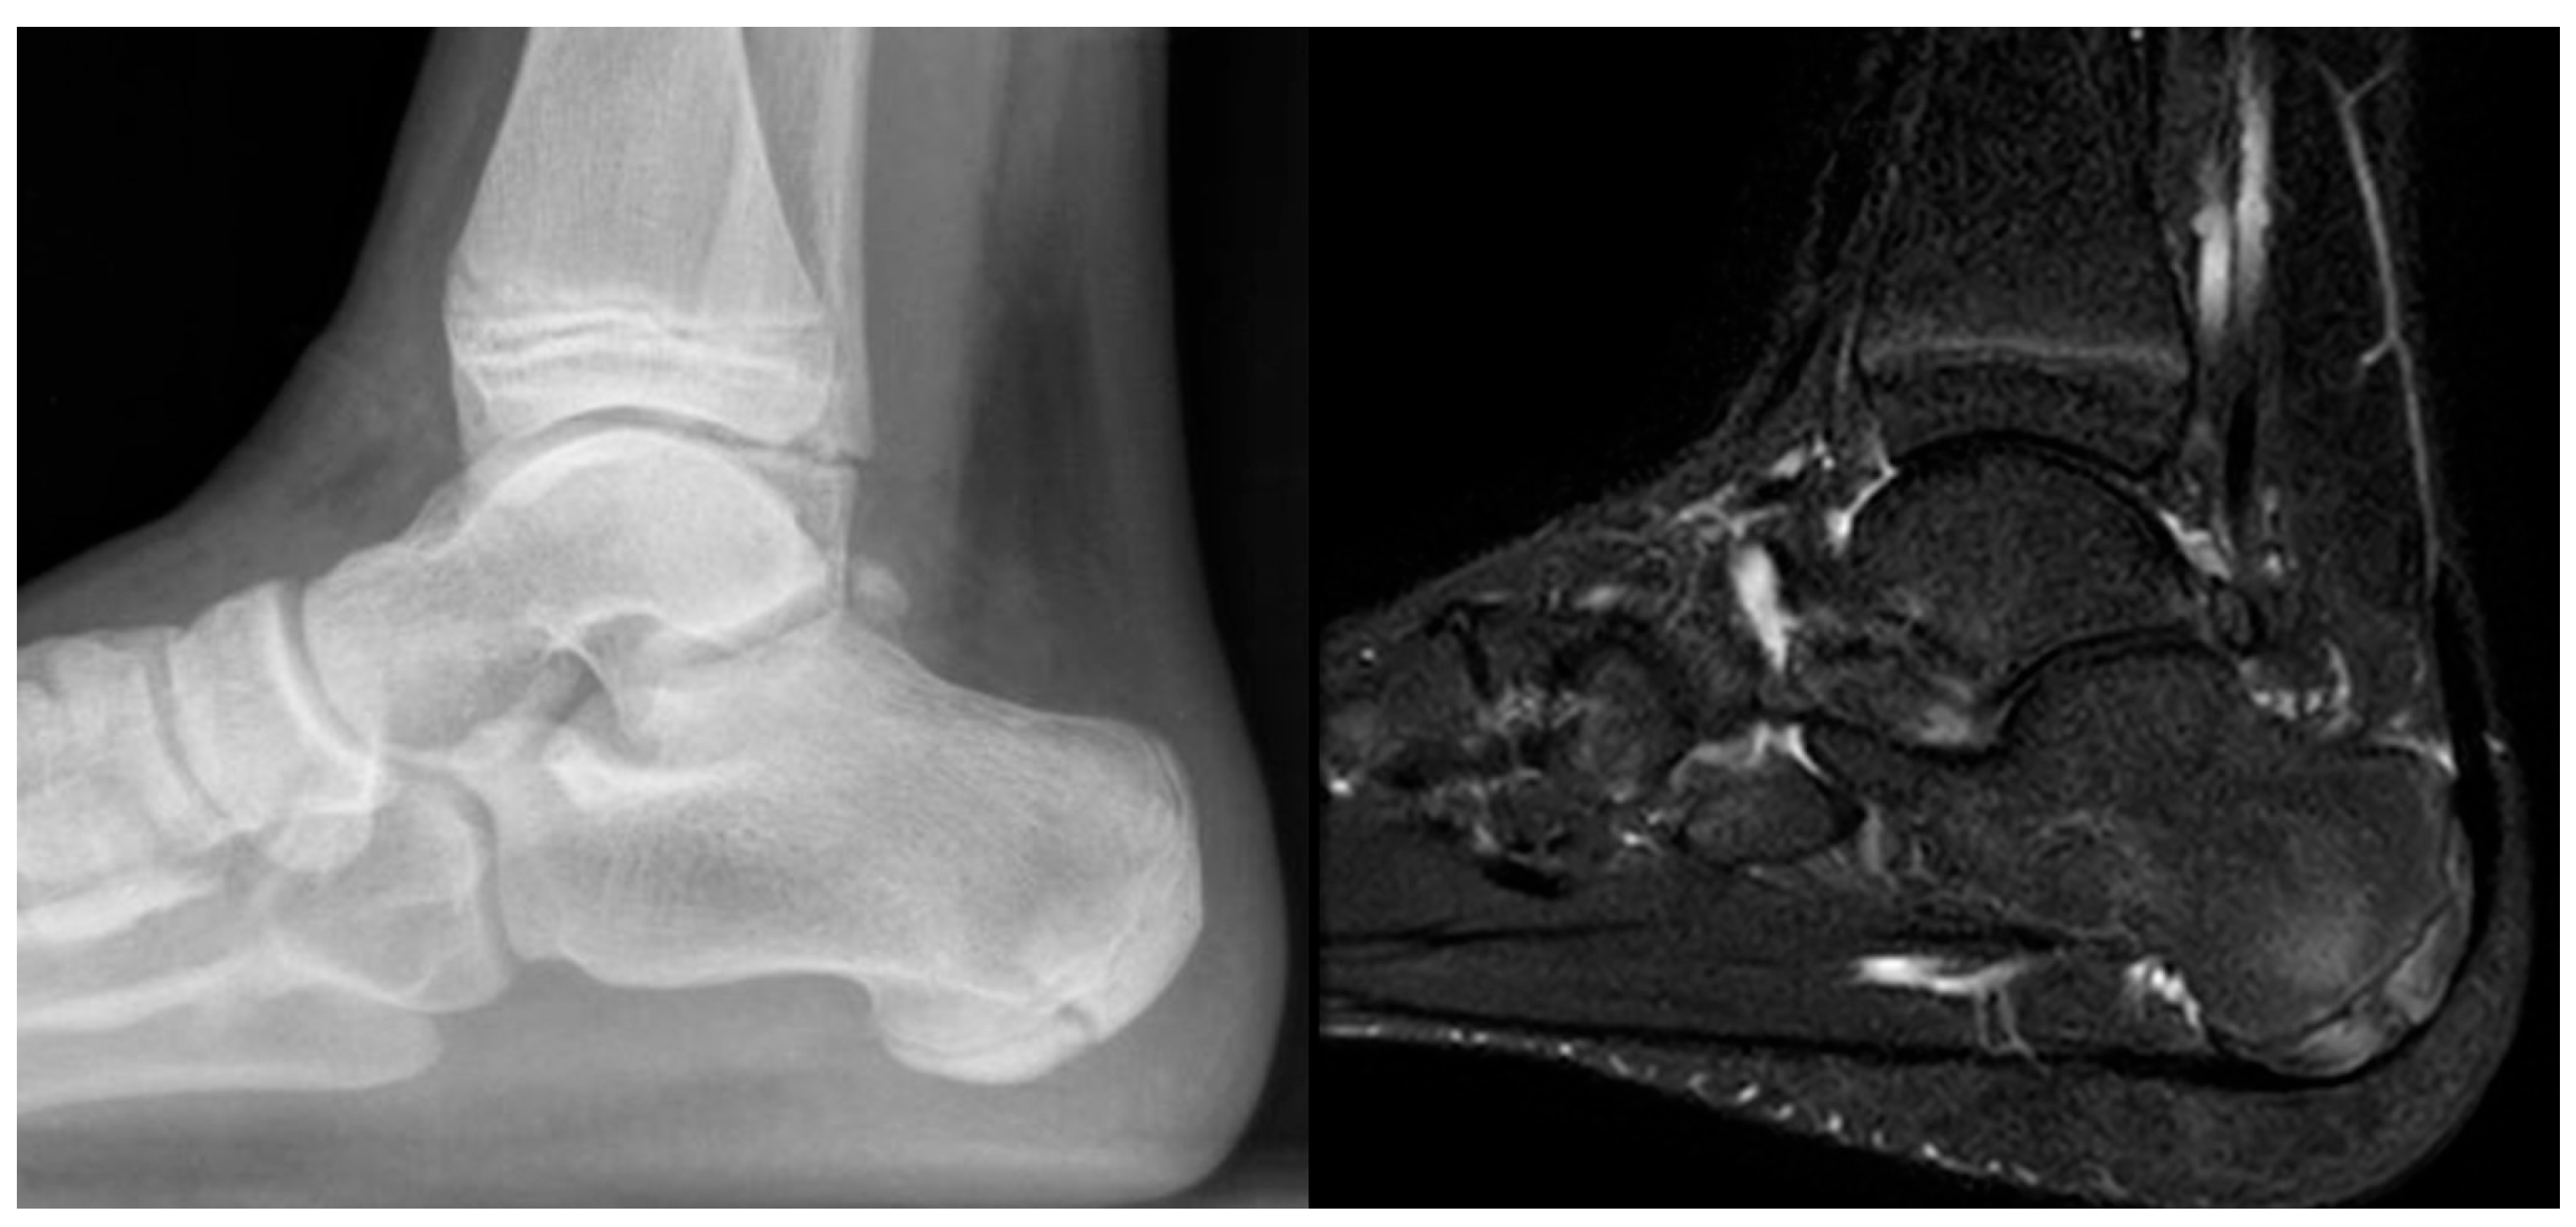

Figure 3.

Eleven-year-old male patient. Radiograph (left) demonstrating typical fragmentation and bipartite appearance of the calcaneal apophysis. MRI (right) showing detailed fragmentation with associated bone marrow edema.

Figure 4.

Ten-year-old male patient. Radiograph (left) revealing marked fragmentation, thinning, and bipartition of the calcaneal apophysis. MRI (right) demonstrating extensive associated bone marrow edema.